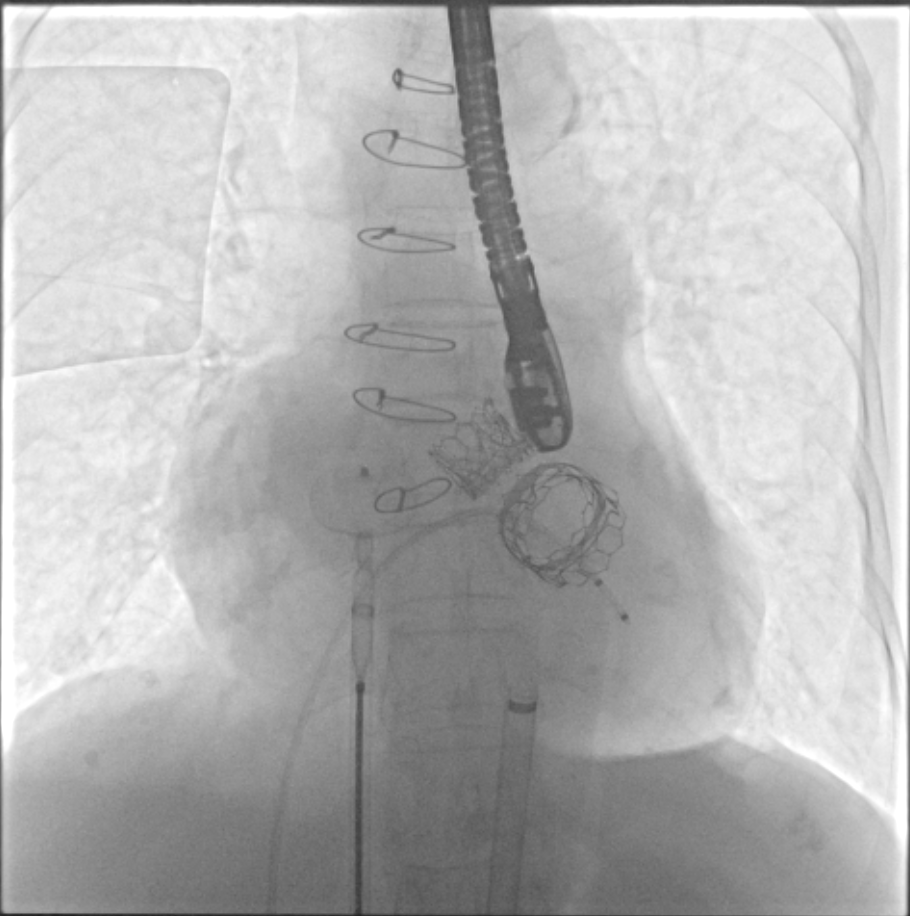

TMVR 术后房间隔封堵

经过充分的术前食道超声及心脏CTA的评估,团队一致选择目前国际上瓣中瓣(Valve in Valve)技术使用最多最成熟的器械——Edwards SAPIEN3瓣膜。与林阿姨及其家属充分沟通后,在经验丰富的王焱院长的指导下,珠海市人民医院结构性心脏病团队决定为林阿姨同期进行主动脉瓣及二尖瓣的双瓣膜置换,采用的方案是先经股动脉途径为其行主动脉瓣的瓣中瓣植入(VinV TAVR),然后经股静脉途径,穿刺房间隔后,行二尖瓣的瓣中瓣植入(VinV TMVR),视情况对房间隔穿刺后的缺损进行封堵。

在经过术前CTA评估测量等检查后,正式手术在珠海市人民医院医疗集团的百级层流复合手术室内进行,在林阿姨全麻的情况下使用食道超声及X线监测指引,经过3小时的紧张手术,双瓣中瓣手术最终成功完成。